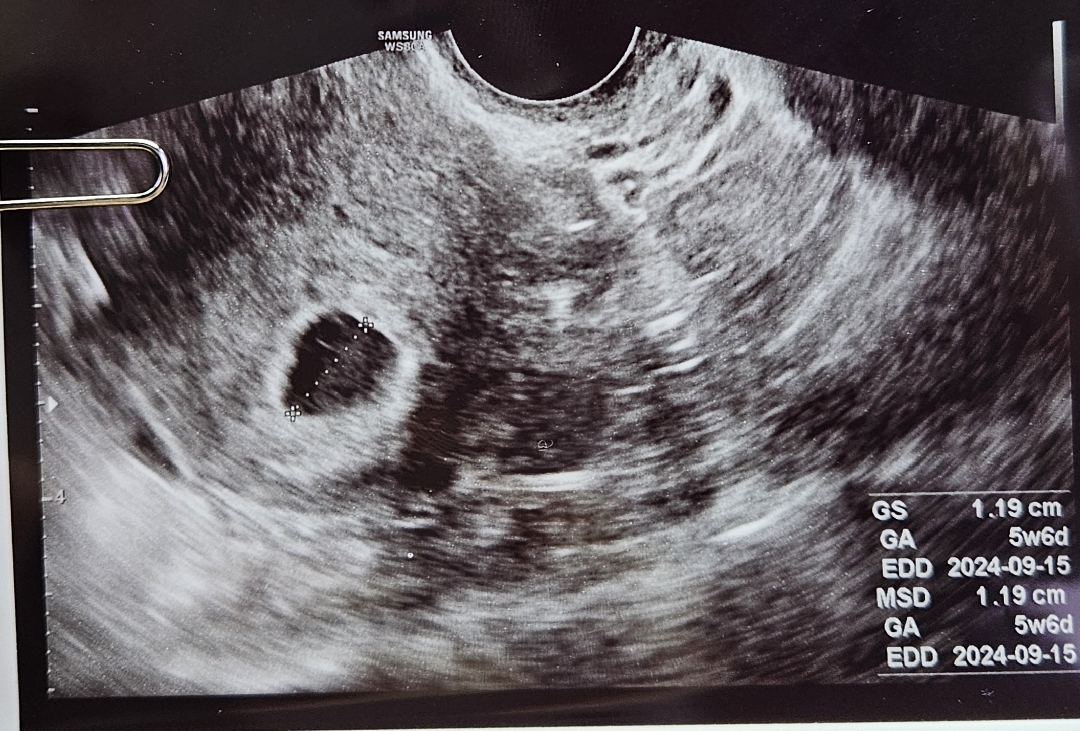

일주일 전 피검사하고 임신이 확실하다고는 했구 오늘 드뎌 초음파 보러 갔다 왔어요ㅎㅎ 전 6주나 됐을까 싶은데 이제 5주 조금 넘은 거 같다고 하시더라구요 난황도 딱 적당한 사이즈라 하시는데 전 뭔지 잘 모르겠어요ㅋㅋ 1cm정도라 하셨구 아주 잘 임신 됐다고 하셔서 마음이 놓이더라구요. 2주 뒤에나 다시 오라고 하셨는데 그 전까지 근데 불안할 거 같아요ㅜㅜ 잘 있겠거니하구 편히 지내야겠죠?? 아기집 사이즈 같은 건 다 다를 수 있는 거죠?? 임신중이신 모든 분들 임신 기간 동안 행복하고 편안하게 지내시길 바라요!ㅎㅎ